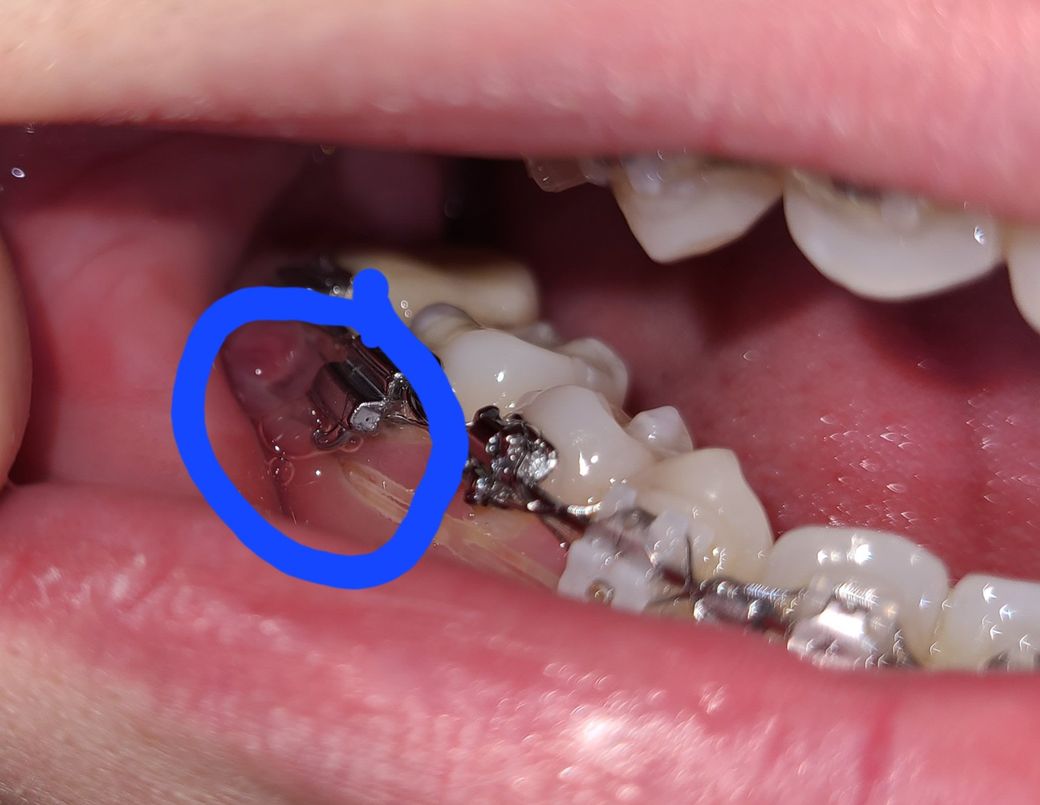

아래쪽만 유독 아프더니 사진과 같이 잇몸이 붓고 스크류를 덮고 연결 된 고무줄 마저 안보일정도 입니다.

잇몸 염증으로 인해 교정용 스크류가 잇몸 하방으로 묻힌 것으로 보입니다.

스크루에 고무줄을 걸어 치아를 당기는 치료를 하는 것으로 보입니다.

스크루 부위에 염증이 생기고 붓는 경우가 종종 있습니다.